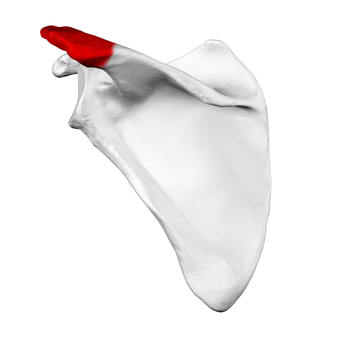

Acromion of scapula06.png

الأخرم (من اليونانية: أكروس، "الأعلى" ōmos، "الكتف"، المفرد: acromia)، هو نتوء عظمي على عظمة الكتف (لوحة الكتف). يمتد الأخرم والناتئ الغرابى جانبياً معاً فوق المفصل الحقاني العضدي. يتمفصل الأخرم مع الترقوة ليكوّنا المفصل الأخرمي الترقوي.

البنية

الأخرم يشكل قمة الكتف، وهو نتوء كبير، شكله مثلث إلى حد ما أو مستطيل، مفلطح من الخلف إلى الأمام، يبرز أوله وحشياُ، ثم يتقوس إلى الأمام و إلى الأعلى، ثم يتعلق مشرفا على التجويف الحقاني.[1]